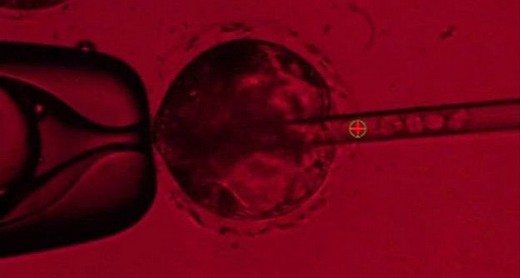

embriyoAmerika Birleşik Devletleri’ndeki bilim insanları, insanlara nakledilmek üzere domuzlarda insan organları geliştirmeyi deniyor. Domuz embriyolarına enjekte edilen kök hücreler ile “chimera” olarak bilinen insan-domuz melezi embriyoları geliştirilme çalışmaları başlatıldı. Bu çalışma, dünya çapında karşılanamayan organ nakli ihtiyacı için bir alternatif bulma arayışının parçası olarak yürütülüyor. California Davis Üniversitesi’ndeki ekip, geliştirilen domuz embriyolarının, normal domuzlara benzer yapıda ve biçimde olduklarını ancak organlarından birinin insan hücrelerinden oluştuğunu söylüyor.

Chimera embriyolarının geliştirilmesi iki aşamada oluyor.

• İlk olarak CRISPR olarak bilinen bir genetik değiştirme yöntemiyle yeni oluşan bir domuz embriyosunun DNA’sı ayrıştırılıyor.

• Sonra da embriyoda oluşan boşluğa gen manipülasyonu yöntemiyle “iPS” denilen hücreler yerleştiriliyor.

Yetişkin bir insandan alınan iPS hücreleri manipüle edilerek kök hücreye dönüştürülüyor ve böylece domuzun vücudunda herhangi bir organa dönüştürülme potansiyeline kavuşuyor. Bu insan kök hücrelerinin domuz embriyosundaki boşluktan faydalanarak embriyonun insan pankreası oluşturması bekleniyor.